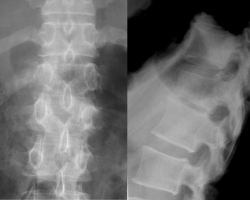

Spondylodiscite tuberculeuse